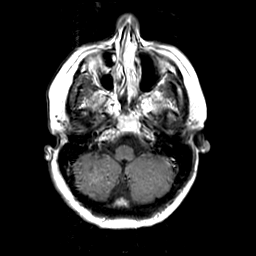

MR Study #3 -- Slice #12